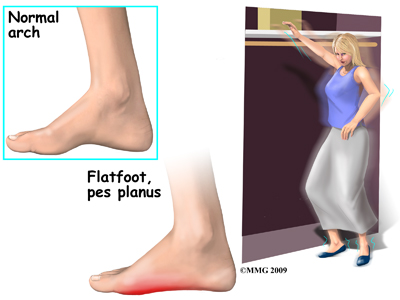

Adult acquired flatfoot deformity (AAFD) is a painful condition resulting from the collapse of the longitudinal (lengthwise) arch of the foot. As the name suggests, this condition is not present at birth or during childhood. It occurs after the skeleton is fully matured.

Obesity has also been linked with this condition. The excess weight causes pressure on the foot, which causes the arch to drop. Misalignment of the lower extremities in obese patients also contributes to the deformity. It should be noted that poor alignment of the lower extremities, in anyone, obese or not, can also progressively lead to AAFD.

At first you may notice pain and swelling along the medial (big toe) side of the foot. This is where the posterior tibialis tendon travels from the back of the leg under the medial ankle bone to the foot. As the condition gets worse, tendon failure may occur, and ligament laxity will worsen, causing the pain to get worse. Some patients also experience pain along the lateral (outside) edge of the foot and ankle, particularly as a deformity develops.

You may find that your feet hurt at the end of the day or after long periods of standing. Some people with this condition have trouble rising up on their toes. They may be unable to participate fully in sports or other recreational activities.

Shoes that have an arch support may relieve your pain, whereas going barefoot will likely increase your discomfort.